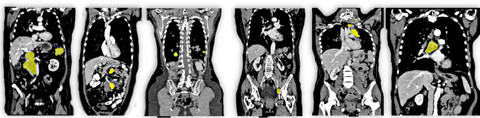

Annotation of whole-body lesions in CT across multiple timepoints

Evaluation of multi-organ CT registration models for lesion tracking across timepoints